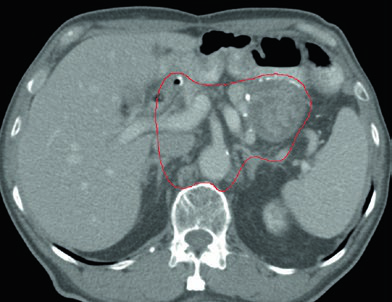

Caso 3: T2N1M0 Adenocarcinoma de Antro/Piloro — Gastrectomia Distal

No adenocarcinoma de antro/piloro, o CTV abrange a anastomose gastrojejunal, o estômago remanescente, o ligamento hepatogástrico e o coto duodenal. A cobertura do hilo esplênico é opcional neste cenário. A inclusão do coto duodenal é preferencial em gastrectomias parciais por tumores distais/antrais, mas não deve ser incluída em pacientes com tumores proximais submetidos a gastrectomia total.